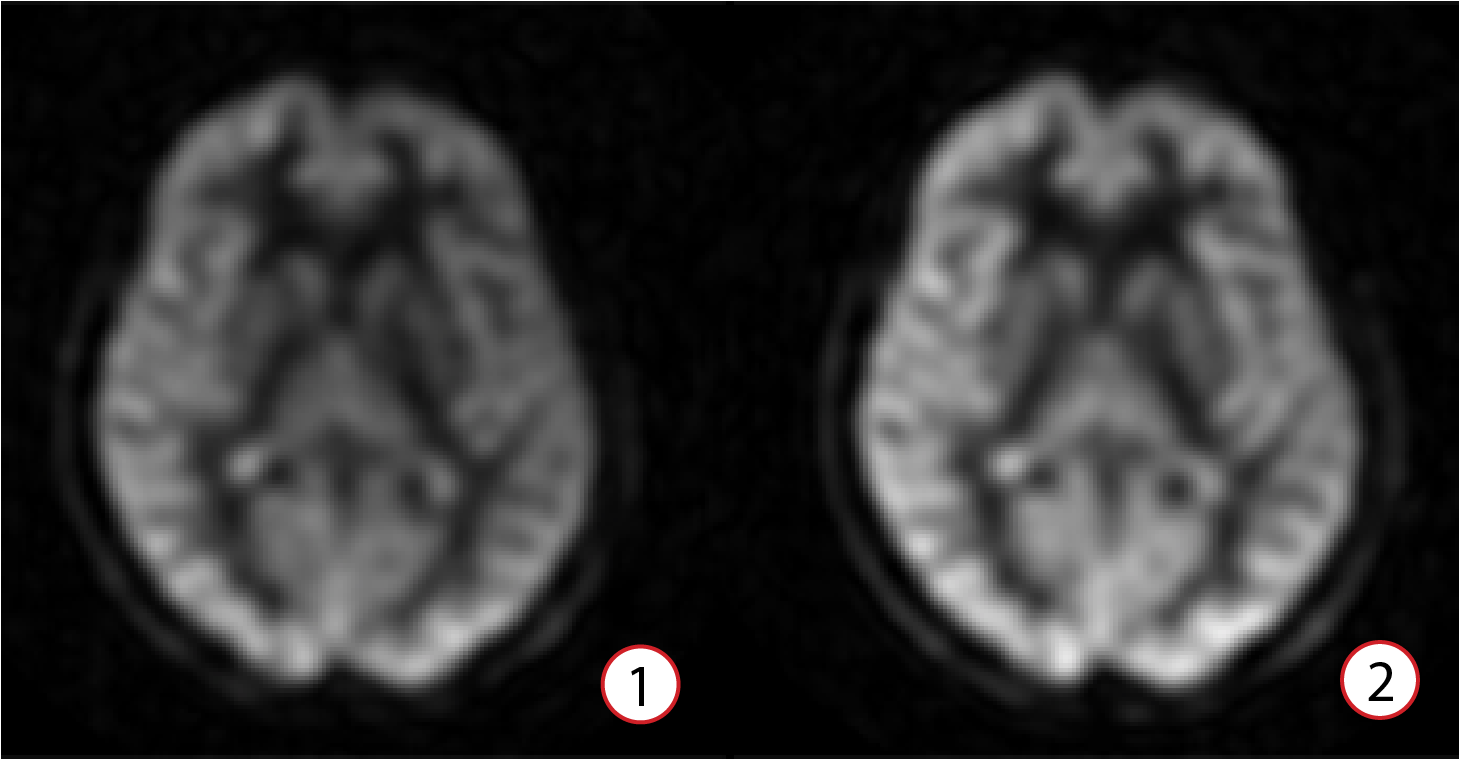

| Number | Description |

|---|---|

| 1 | Flexible Labeling Mode disabled Label duration = 1450 ms |

| 2 | Flexible Labeling Mode enabled Label duration = 2000 ms |